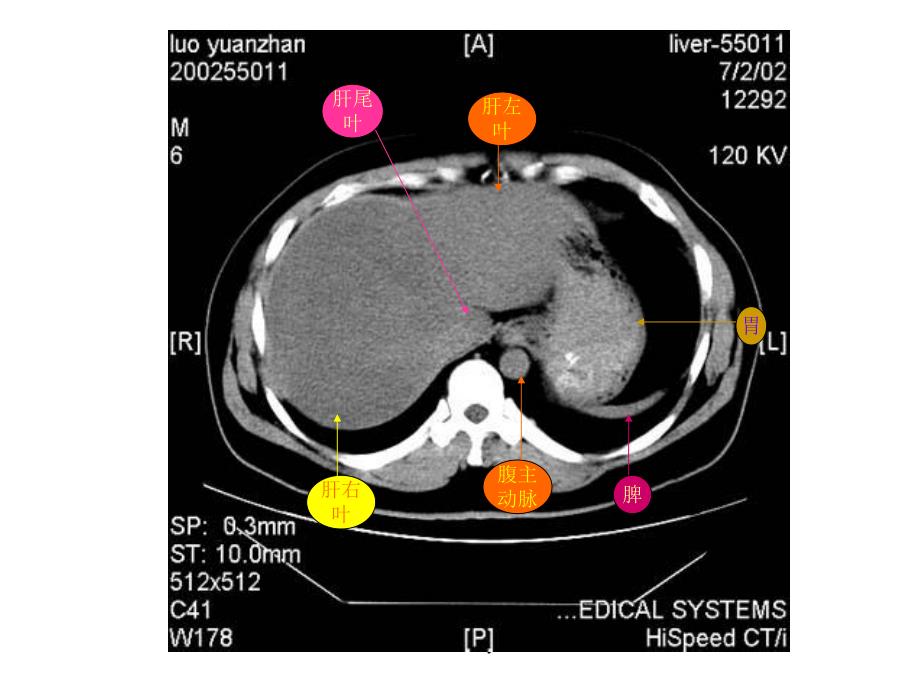

1、博益园 肝右叶横膈肺胸椎脊髓腹主动脉食管肋骨博益园 肋骨肝右叶腹主动脉食管肺博益园 肝左叶肝右叶腹主动脉胃脾肝尾叶博益园 肝右叶尾叶膈脚脾门静脉肝左叶胃博益园 肝右叶膈脚腹主动脉脾胆囊胃博益园 肝右叶下腔静脉胰腺脾胃腹主动脉博益园 肝右叶心脏腹主动脉下腔静脉脊髓食管肺博益园 肝左叶肝右叶腹主动脉下腔静脉胃脾脊髓博益园 肝左叶及肝左动脉肝右叶及肝右动脉腹主动脉下腔静脉胃脾肝尾叶博益园 肝右叶下腔静脉腹主动脉胃脾膈脚博益园 肝静脉下腔静脉腹主动脉食道肝右叶博益园 下腔静脉肝右叶肝静脉肝左叶腹主动脉胃脾肝尾叶博益园 肝右叶下腔静脉腹主动脉门静脉主干肝左叶胃脾博益园 肝右叶下腔静脉门静脉腹主动脉膈脚脾